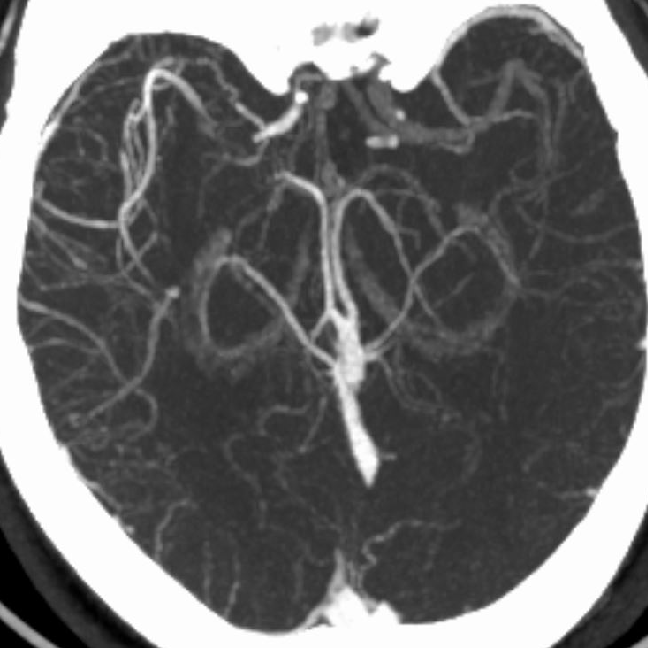

术前CTA:

CTA提示右侧大脑中动脉闭塞,左侧A1纤细。